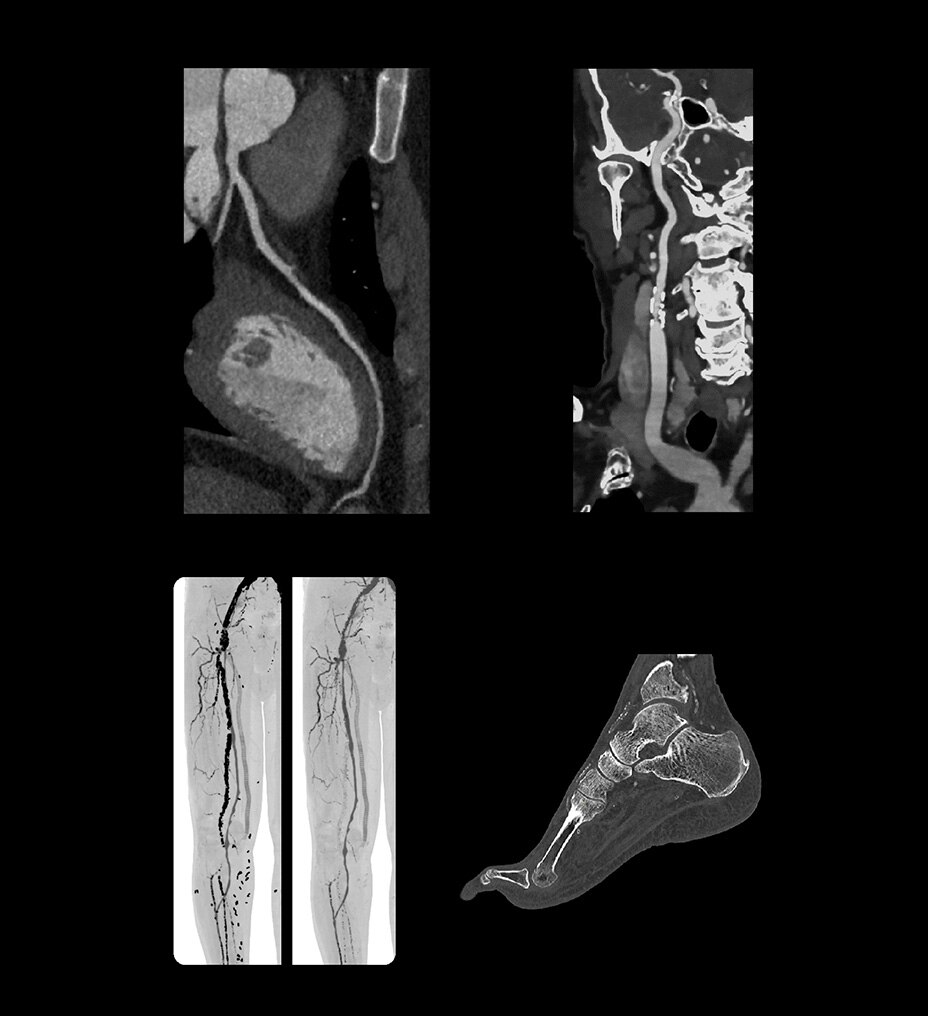

Birden fazla uygulamada çok yönlülük

Revolution Ascend; rutin, kardiyak, büyük bedenli hasta, Acil Servis ve girişimsel dahil olmak üzere çoğu ortama yönelik özelliklere sahiptir.

BT deneyiminin en çok zaman alan kısmı taramanın kendisi değil; hastayı hazırlama, rekonstrüksiyon ve raporlama süresi gibi taramanın dışında kalan adımlardır. BT deneyimindeki tüm tarama öncesi ve tarama sonrası adımları analiz ettik ve önemli bulgularımızı Revolution Ascend'in tasarımına dahil ettik. Bu tasarımının sonucunda Revolution Ascend, yüksek BMI değerine sahip hastaları ve girişimsel prosedürleri verimli bir şekilde yönetebilme gibi yaygın endişeleri ortadan kaldırır. Ayrıca, tüm görüntüleme modları için kullanımı kolay iki düğmeli tarama sağlar.